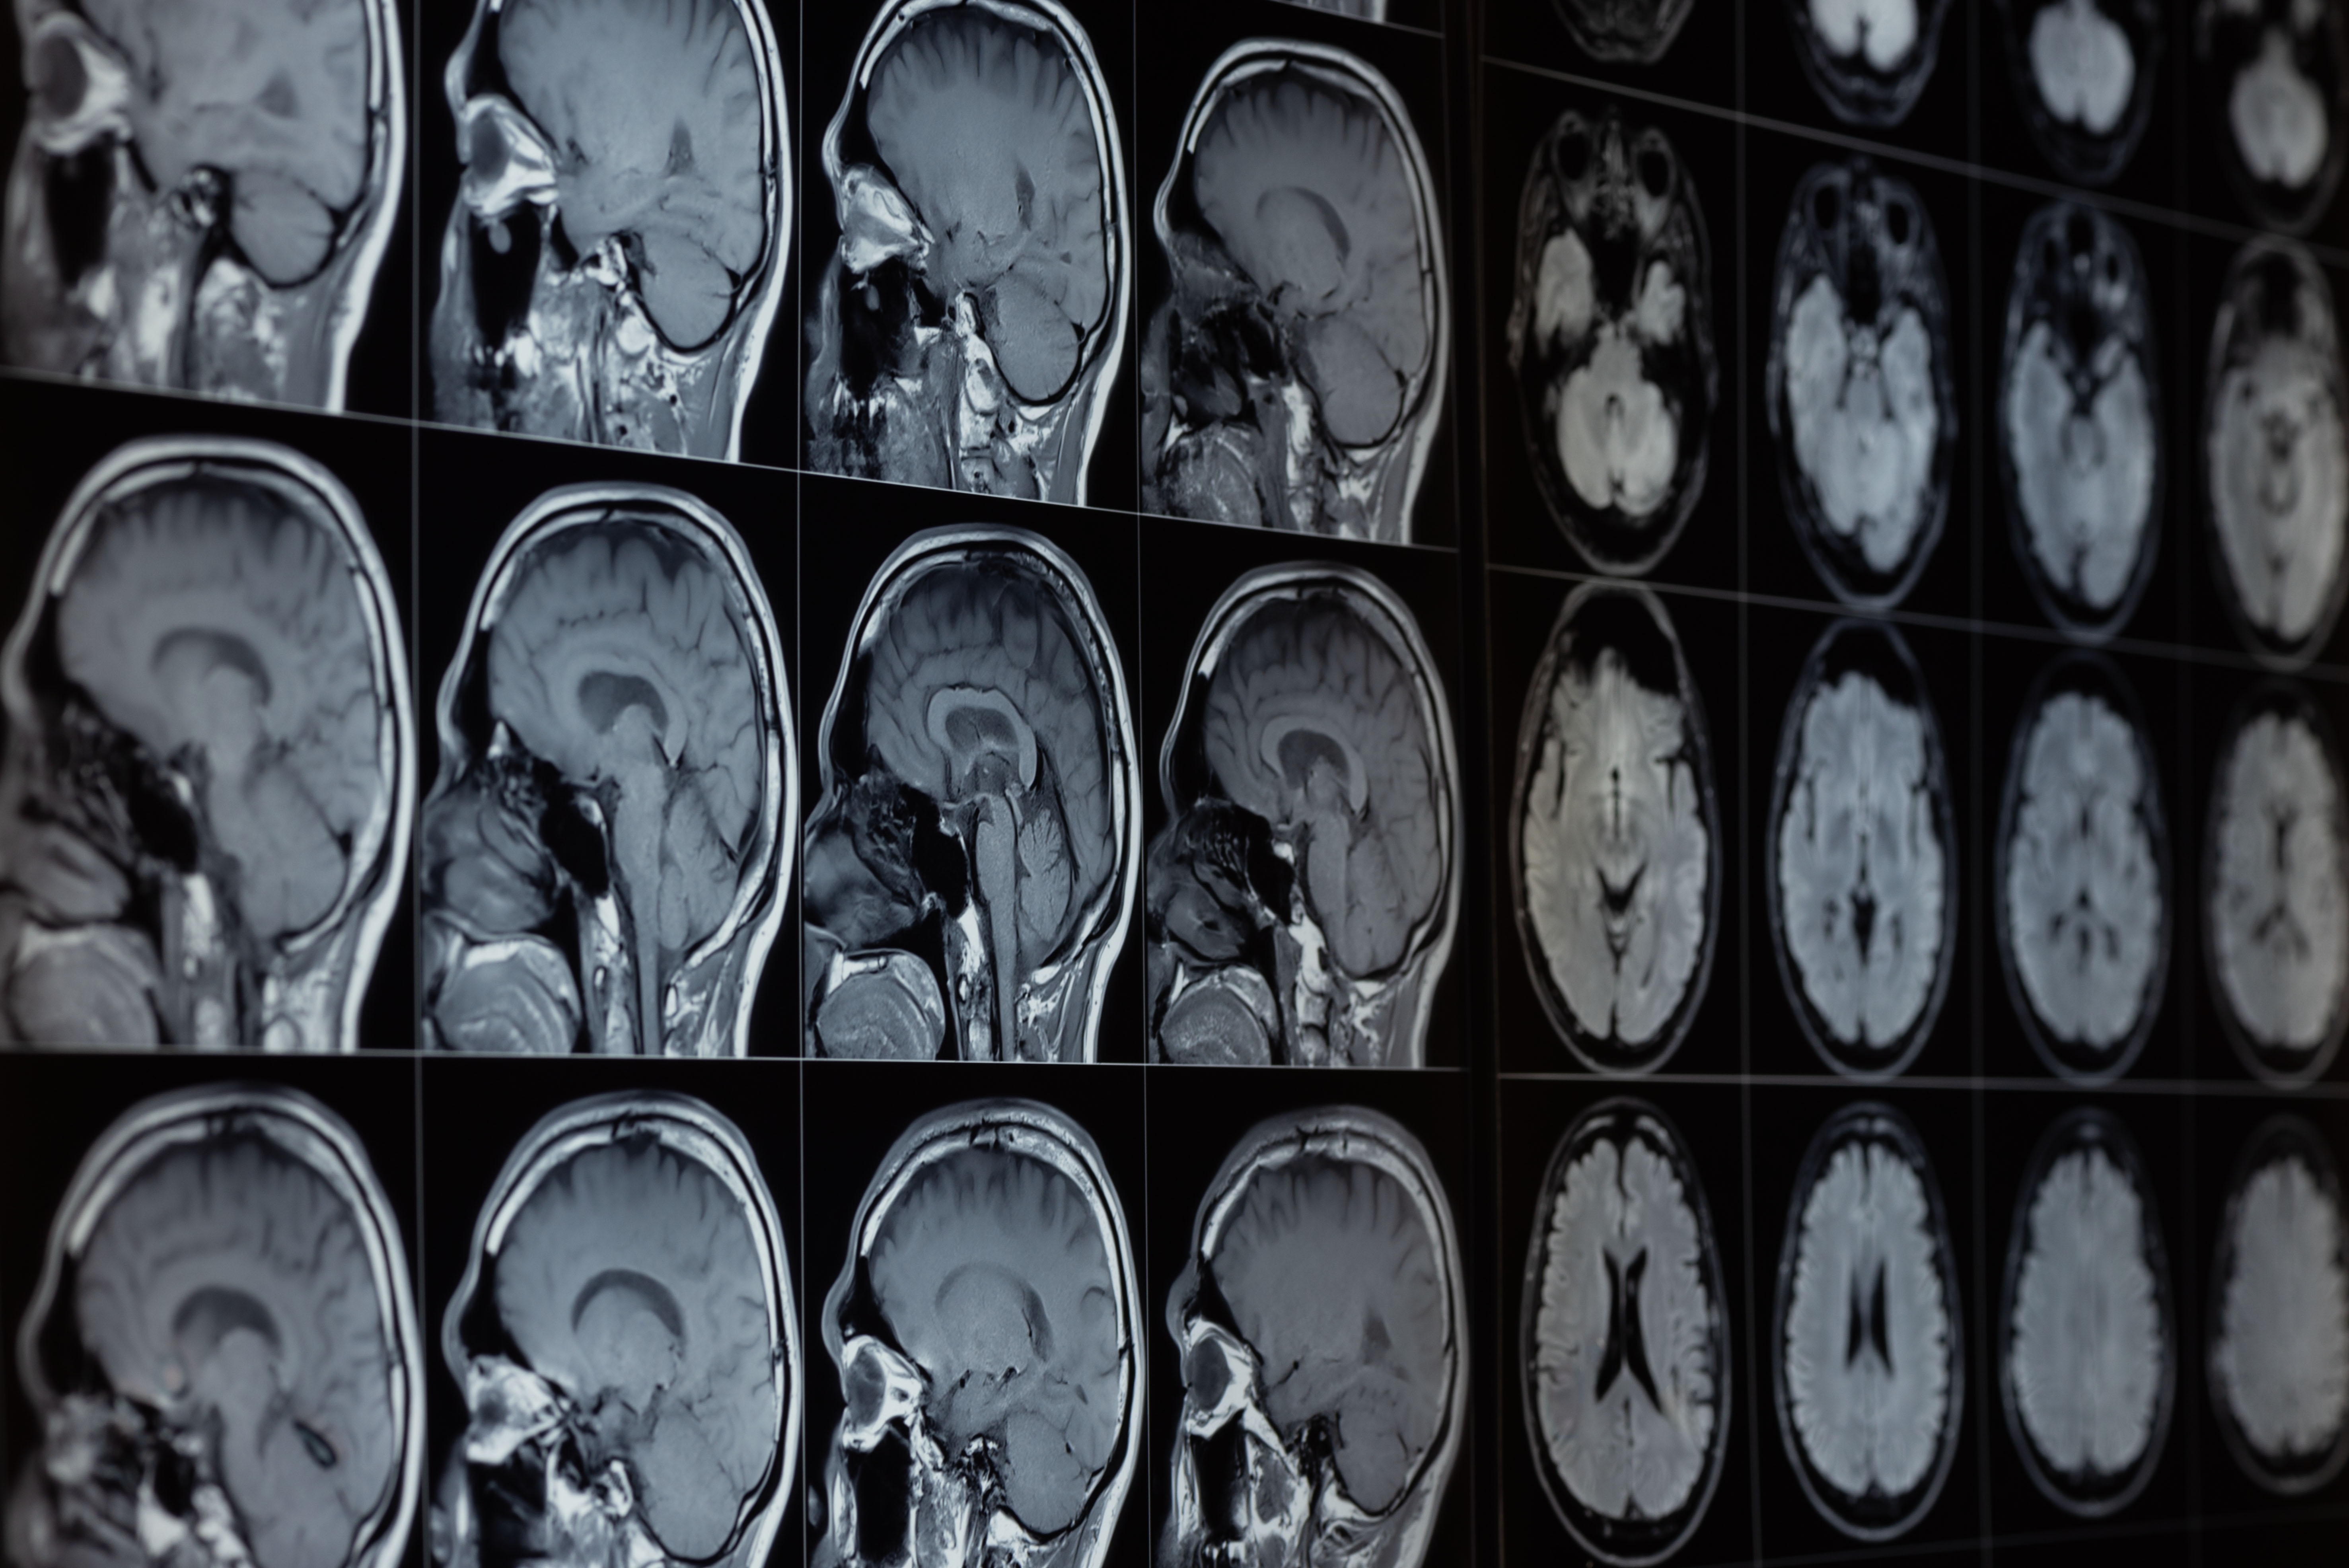

有时大脑会让你看到奇怪的东西。正在通过将电极带植入他的梭状回进行实验性治疗癫痫症——该区域在视觉和模式识别中发挥着关键作用。

研究人员向梭状面部区域发送电脉冲,患者开始看到到处都是虚幻的面孔,包括人的真实面孔。这些幻觉被科学团队称为“facephenes”,然而,只有某些人才能看到这一点。

大脑…

图片来源:Teeradej/Shutterstock.com

其他研究人员做了实验来诱导有人在附近。他们通过刺激大脑左半球的一个部位来做到这一点。这位22岁的患者正在接受癫痫治疗的评估,当她的大脑部分受到刺激时,她感觉有人在她身后,将这个“人”描述为一个“影子”,没有移动或说话,就在后面,年轻且性别不确定。

这并不是第一次这样做。还有一个机器人,也让人感觉背后有鬼。工作中,由于他们所经历的时空冲突,机器人可以让健康的参与者感觉有人(或某物)站在他们身后。

根据这项研究,神经科学家奥拉夫·布兰克决定对患有神经系统疾病的人进行研究,因为有些疾病会导致人们看到幽灵。约 50%的人有(一种导致大脑部分多年来受损越来越严重的疾病)报告说他们经历了幻觉。它们影响女性和男性,幻觉的范围很广,从眼角的余光看到的东西到完全形成的彩色视觉幻觉。

研究小组使用同一机器人的改进版本,试图诱发帕金森病患者出现幻觉。当研究小组刺激大脑的不同区域时,患者会感觉到背后有一个存在或“幽灵”。研究发现,那些预先存在幻觉的患者比没有任何幻觉经历的患者具有更高的敏感性。这项研究意味着大脑颞叶和额叶之间的通讯中断可能是帕金森病患者出现幻觉的原因。